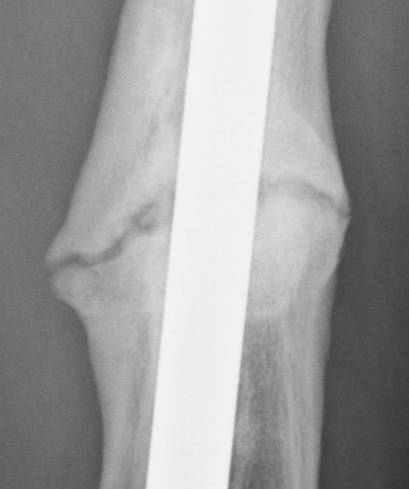

June 22, 2010 X-ray update

Forive me people for I have sinned. It has been two years since my last update. But seriously, there is much improvement to report. Based on activity and how it feels things are progressing very well. The x-rays also show more bone growth which adds to the good sign.

Feb. 21, 2008 June 22, 2010